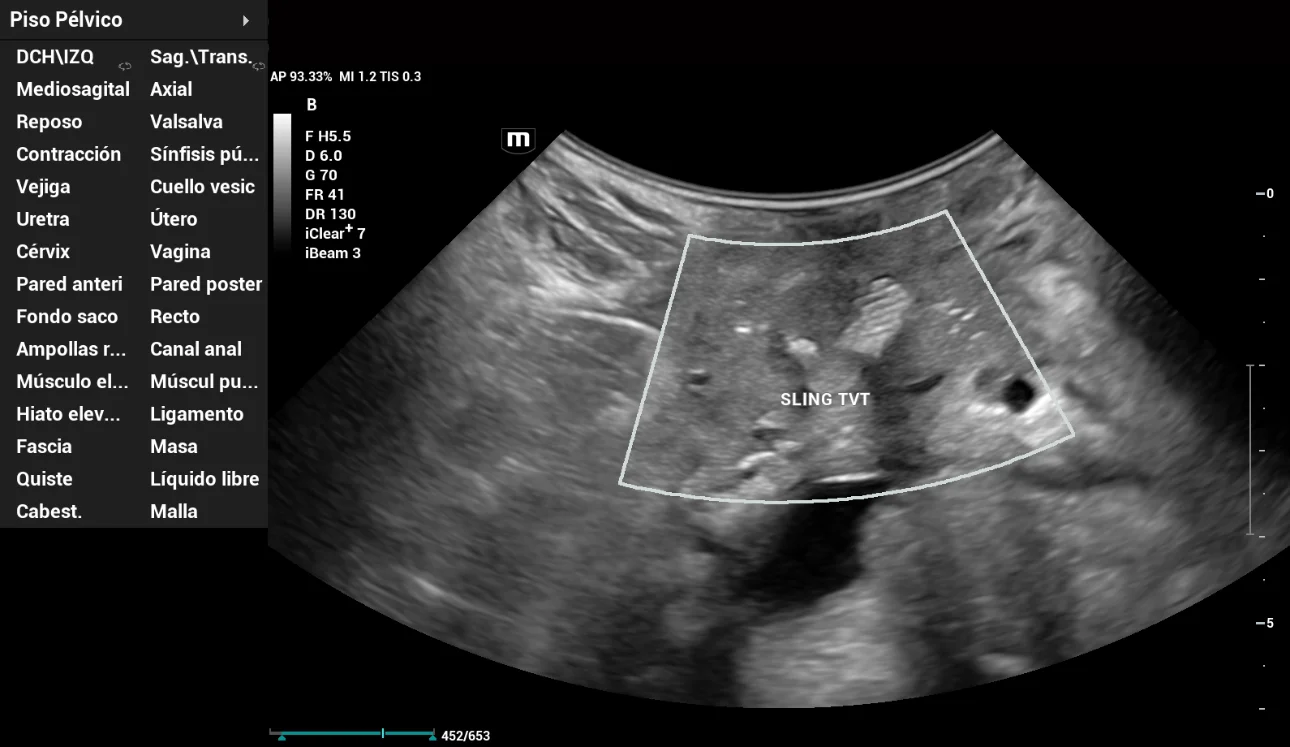

A periurethral evaluation was performed with an image suggestive of a MUS with a vertical vector (TVT), located at the junction of the middle and external urethral thirds (Figure 8).

The evaluation parameters of the MUS were: distance to the urethra 5mm (R); distance to the urethral meatus 4mm (R), 3mm (Val); distance to the bladder neck 16mm (R), 13mm (Val); pubic sling gap 17mm (R), 14mm (Val). No presence of prolapse mesh.

pelvic-floor-ultrasound-stress-incontinence-fig8

Figure 8: Presence of vertical vector sling (TVT) evaluated with HD Scope tool